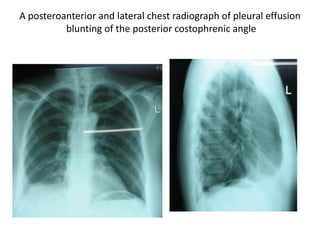

A posteroanterior and lateral chest radiograph of pleural effusion

blunting of the posterior costophrenic angle

A posteroanterior andlateral chest radiograph of pleural effusion blunting of the posterior costophrenic angle